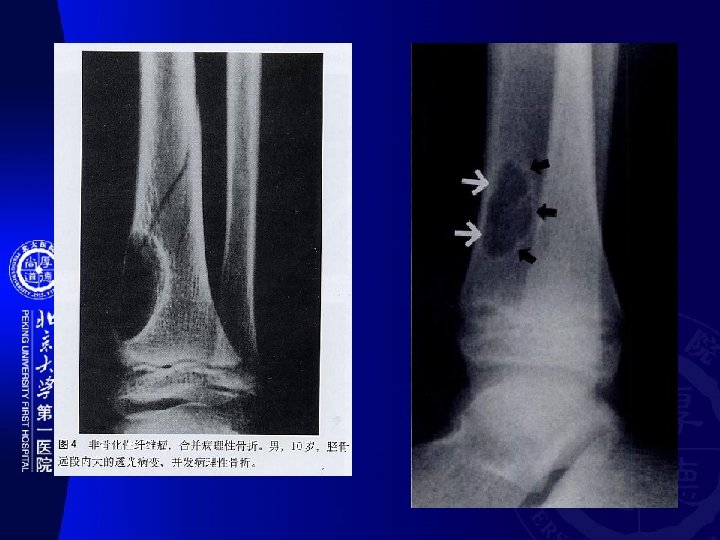

骨干 Diaphysis 干骺端 Metaphysis 骨骺 Epiphysis Other Myeloid 多发性骨髓瘤(Multiple myeloma) Epithelial 釉质细胞瘤(Adamantinoma) PNET 尤文氏瘤 (Ewing’s sarcoma) Osteoblast 骨样骨瘤 成骨细胞瘤(Osteoblastoma) 骨瘤 (Osteoma) 骨肉瘤(Osteosarcoma) Chondroblast 软骨瘤 软骨肉瘤(Chondrosarcoma) 骨软 骨瘤 软骨粘液样纤维瘤 Fibrous 非骨化性纤维瘤(nonossifying fibroma) 纤 维肉瘤(Fibrosarcoma) Chondroblast 成软骨细胞瘤(Chondroblastoma) Myeloid 骨巨细胞瘤(Giant cell tumor of bone) Notochord 脊索瘤(Chordoma)

� 骨好� 部位(SITE OF LONG BONE INVOLVEMENT ) (most primary bone tumors have favored sites within long bones; this may provide a clue to diagnosis). Diaphyseal intramedullary lesions: Diaphyseal lesions centered in the cortex: 釉� 瘤, 骨� 骨瘤 尤文氏瘤,淋巴瘤, 骨髓瘤,� �� 构不良,内生� 骨瘤 Metaphyseal intramedullary lesions: 骨肉瘤、� 骨肉瘤、 �� 肉瘤、�� 性骨囊� 、 � 脉瘤� 骨囊� Metaphyseal lesions centered in the cortex: 非骨化性�� 瘤(NOF) Epiphyseal lesions: � 骨母� 胞瘤 (Ch) and 骨巨 � 胞瘤(GCT) Metaphyseal exostosis: 骨� 骨瘤